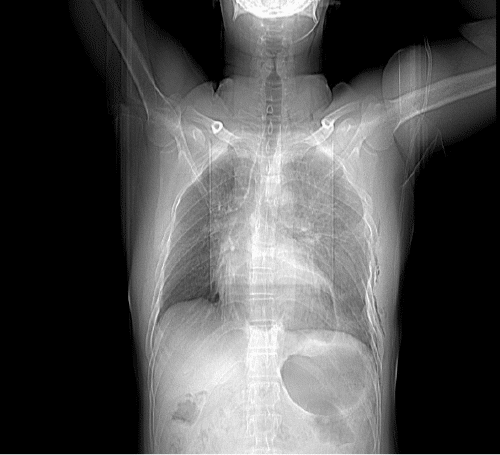

The patient was admitted to the intensive care unit (ICU) for further assessment before the surgery; his blood pressure was approximately 90/50 mmHg, and his pulse rate was 120 beats/min, which might be related to the herniated stomach inside the pericardial cavity, causing cardiac tamponade with hypotension and tachycardia. The nasogastric tube (NGT) was inserted, and approximately 300 mL (0.3 × 10-3 m3) of gastric content was aspirated. The patient felt better, which could be related to the reduction of the herniated stomach inside the abdominal cavity from the pericardial space. A few minutes later, his blood pressure increased to 105/75 mmHg, and his pulse rate decreased to 100 beats/min. A portable chest X ray film showed the absence of gastric gas in the pericardial space and NGT in the stomach (Figure 3).

Figure 3. Portable Chest Radiography Showing Absence of Gastric Gas in Pericardium After Inserting Nasogastric Tube. Published with Permission